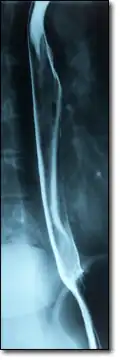

Эндоскопия пищевода пациента с варикозным расширением вен пищевода

При исследовании печени, поджелудочной железы и жёлчных протоков ведущую роль занимают ультразвуковые исследования (УЗИ), компьютерная томография (КТ) и магнитно-резонансная томография (МРТ). При диагностике состояния пищевода распространено рентгеновское исследование с барием, при котором прохождение глотков бариевой взвеси регистрируется флюороскопически в реальном масштабе времени. Рентгенография пищевода применяется для выявления грыж пищеводного отверстия диафрагмы, опухолей, дивертикулов, стриктур, варикозного расширения вен, инородных тел. Рентгенография или рентгеноскопия с двойным контрастированием или без него применяется при исследовании желудка и двенадцатиперстной кишки с целью выявления язв, опухолей, стриктур, обтураций, контроля результатов оперативных вмешательств. Для диагностики опухолей кишечника, воспалительных заболеваний, причин непроходимости кишки, стриктур, обструкции применяется контрастная рентгенография, компьютерная или магнито-резонансная томография[28].